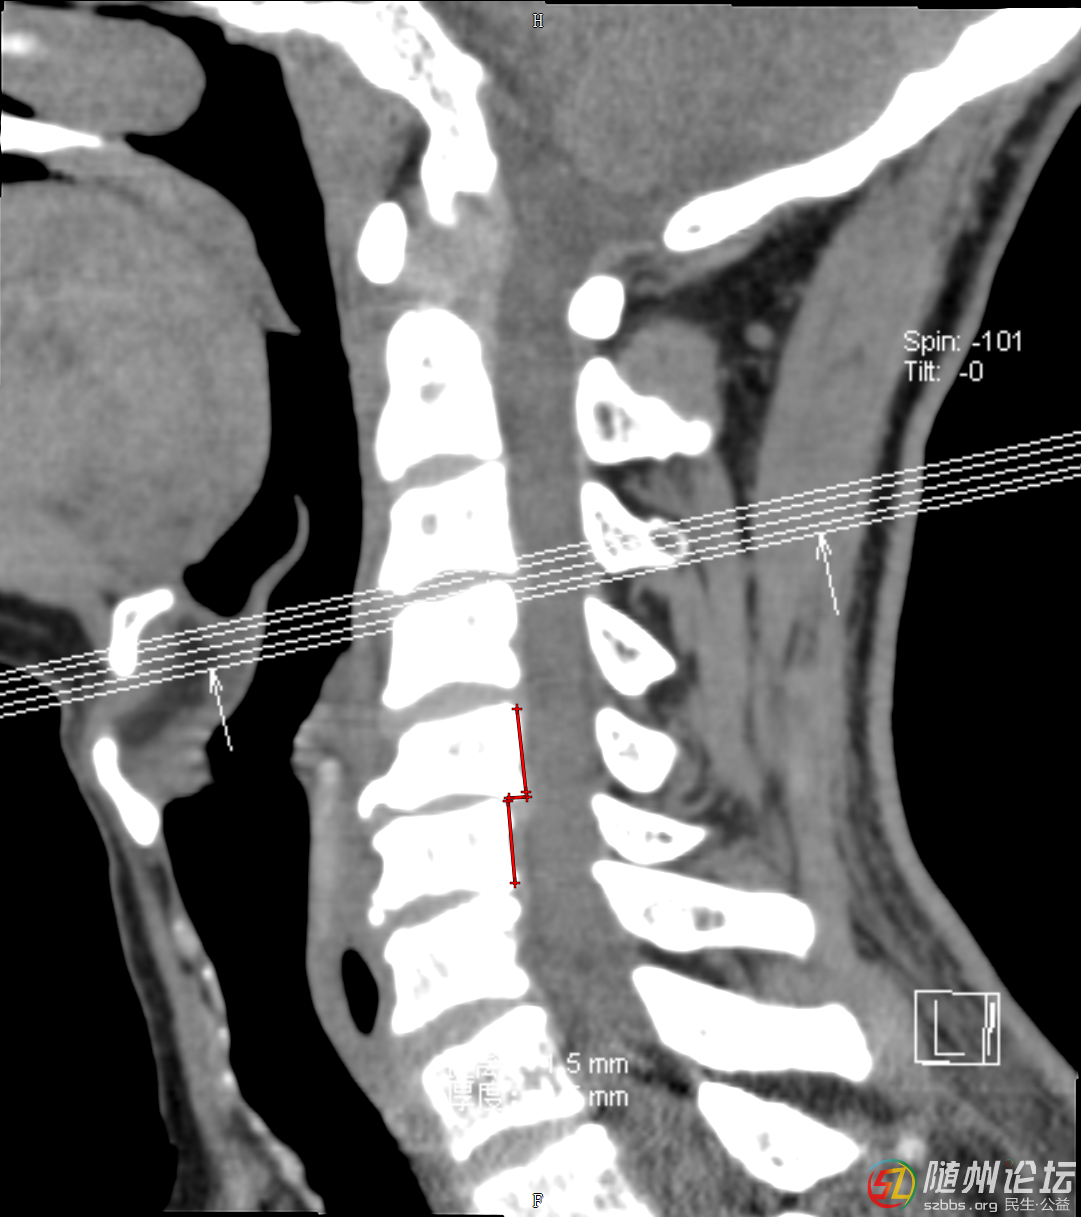

入院后,醫(yī)院醫(yī)務(wù)處迅速組織脊柱外科、康復(fù)醫(yī)學(xué)科、麻醉科、神經(jīng)外科等多學(xué)科專(zhuān)家楊旭、黃明勇、汪兵、程勇等進(jìn)行四級(jí)手術(shù)術(shù)前多學(xué)科討論。專(zhuān)家們?cè)敿?xì)研究患者病情,結(jié)合影像學(xué)檢查結(jié)果,制定了個(gè)性化的治療方案??紤]到脊髓損傷的復(fù)雜性和緊迫性,決定首先為患者實(shí)施頸椎脊髓減壓和內(nèi)固定手術(shù),以解除脊髓壓迫,穩(wěn)定脊柱結(jié)構(gòu),為后續(xù)康復(fù)創(chuàng)造條件。

患者術(shù)前影像學(xué)圖片